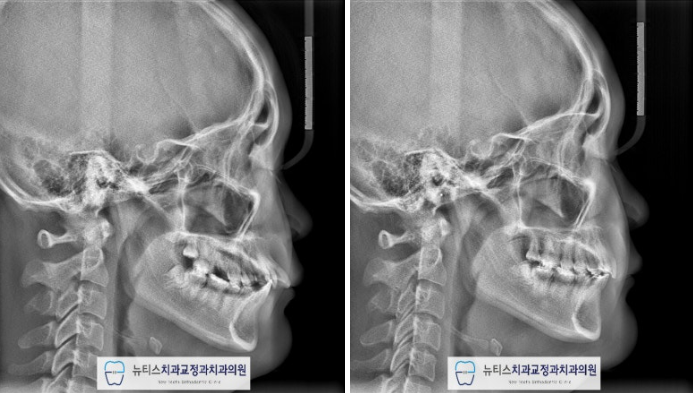

¹æ»ç¼± »çÁø¿¡¼µµ º¸½Ã¸é

µ¹ÃâµÈ ¾Õ´Ï°¡ ¾çÈ£ÇØÁø ºÎºÐÀ» º¼ ¼ö ÀÖ½À´Ï´Ù.